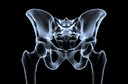

O quadril é uma junta formada pela cabeça1 do fêmur2 que se articula com uma cavidade da bacia chamada acetábulo3 (articulação4 coxofemoral). A artroplastia do quadril é uma cirurgia que substitui essa articulação4, quando doente, danificada ou fraturada, por uma prótese5 de metal, polietileno ou cerâmica, capaz de devolver sem dor as atividades de vida diária que haviam sido comprometidas.